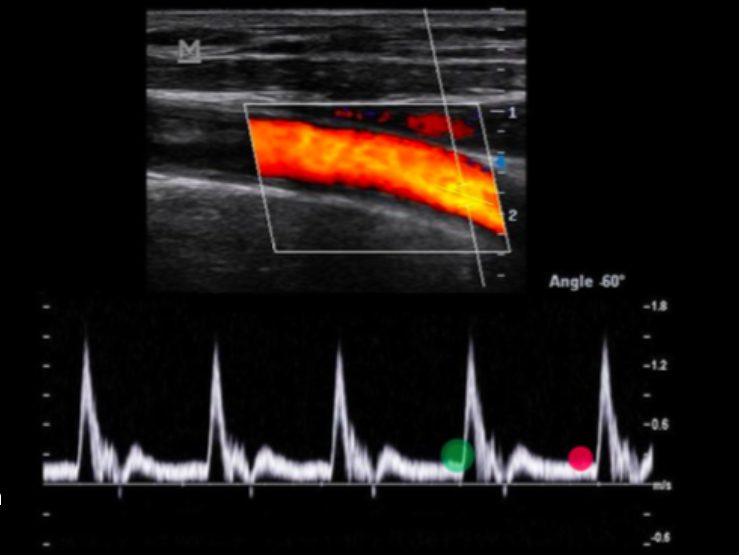

Use your cursor to measure the end diastolic velocity of the third waveform. Use your mouse to position the cursor and click to set your answer.

(green)